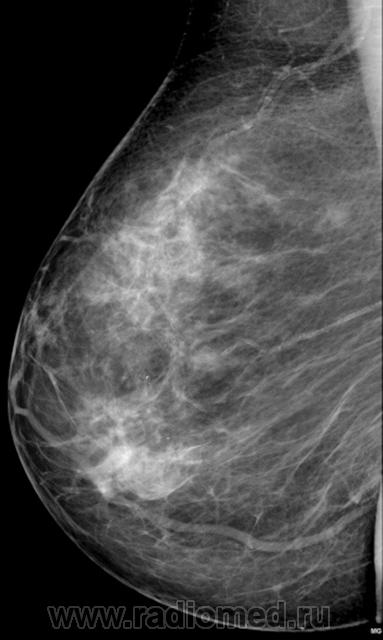

травма правой молочной железы

Пациентку укусила собаки. Видна явная асимметричная рентген.картина за счет очагов фиброза в верхне-наружном квадране правой молочной железы

Данная картина может рассматриваться как "смешанная ФКМ"?

Тут конечно больше  инволюционных изменений с преобладанием фиброза,  хотя сохранена  слабо выраженная  железистая ткань в центральных областях.